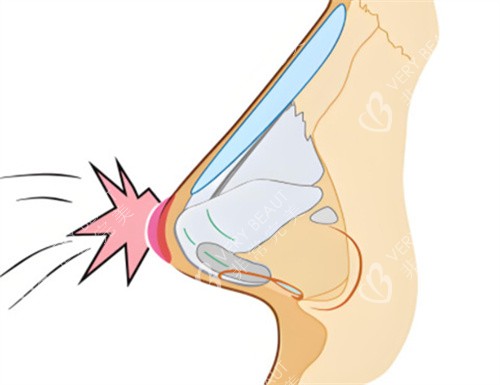

鼻修复费用

鼻修复手术的难度和复杂程度要远远高于初次隆鼻手术。这是因为之前的手术可能已经对鼻部组织造成了一定的损伤,需要医生更加谨慎地处理。鼻修复的费用波动较大,一般在20000 - 50000元。具体的费用会根据修复的原因、修复的部位以及修复的难度来确定。如果只是轻微的形态调整,费用可能相对较低;但如果是出现了感染、假体移位等问题,修复的难度和费用都会相应增加。